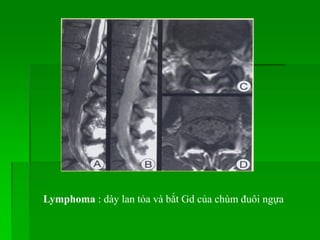

Lymphoma

- Thường gặp ở 40-60 tuổi, nam >nữ.

- MRI: tín hiệu thấp trên T1W, cao không đồng nhất trên T2W,

bắt Gd sau tiêm, có thể gây hủy xương hay chèn ép tủy.

Lymphoma : dày lan tỏa và bắt Gd của chùm đuôi ngựa

Lymphoma - Thường gặpở 40-60 tuổi, nam >nữ. - MRI: tín hiệu thấp trên T1W, cao không đồng nhất trên T2W, bắt Gd sau tiêm, có thể gây hủy xương hay chèn ép tủy.

• 111.

Lymphoma : dàylan tỏa và bắt Gd của chùm đuôi ngựa